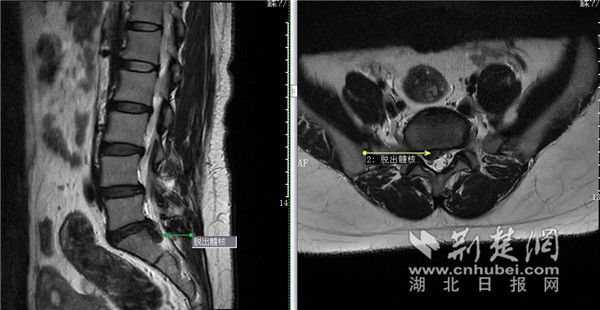

冯女士核磁影像图。通讯员供图

该科副主任医师滕宇对其进行了细致检查,结合核磁共振结果,发现其几处腰椎关节有不同程度骨质增生改变和松动不稳,椎间盘膨出、脱出,尤其是腰5骶1脱出的巨大椎间盘严重压迫了硬膜囊和神经根,诊断其为腰椎间盘脱出伴坐骨神经痛。